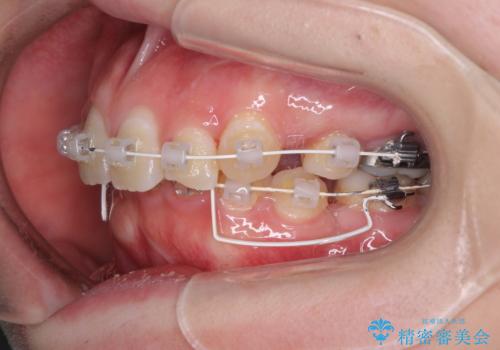

- 審美装置

下顎小臼歯の欠損により過蓋咬合となっていたため、下顎は臼歯を起こすことで咬み合わせを改善し、八重歯は第一小臼歯2本を抜歯し、補助装置を使用して速やかに改善することとしました。

著しい過蓋咬合の改善が必要であった割には、治療期間は2年強と標準的でした。

八重歯は3,4か月で速やかに改善されました。